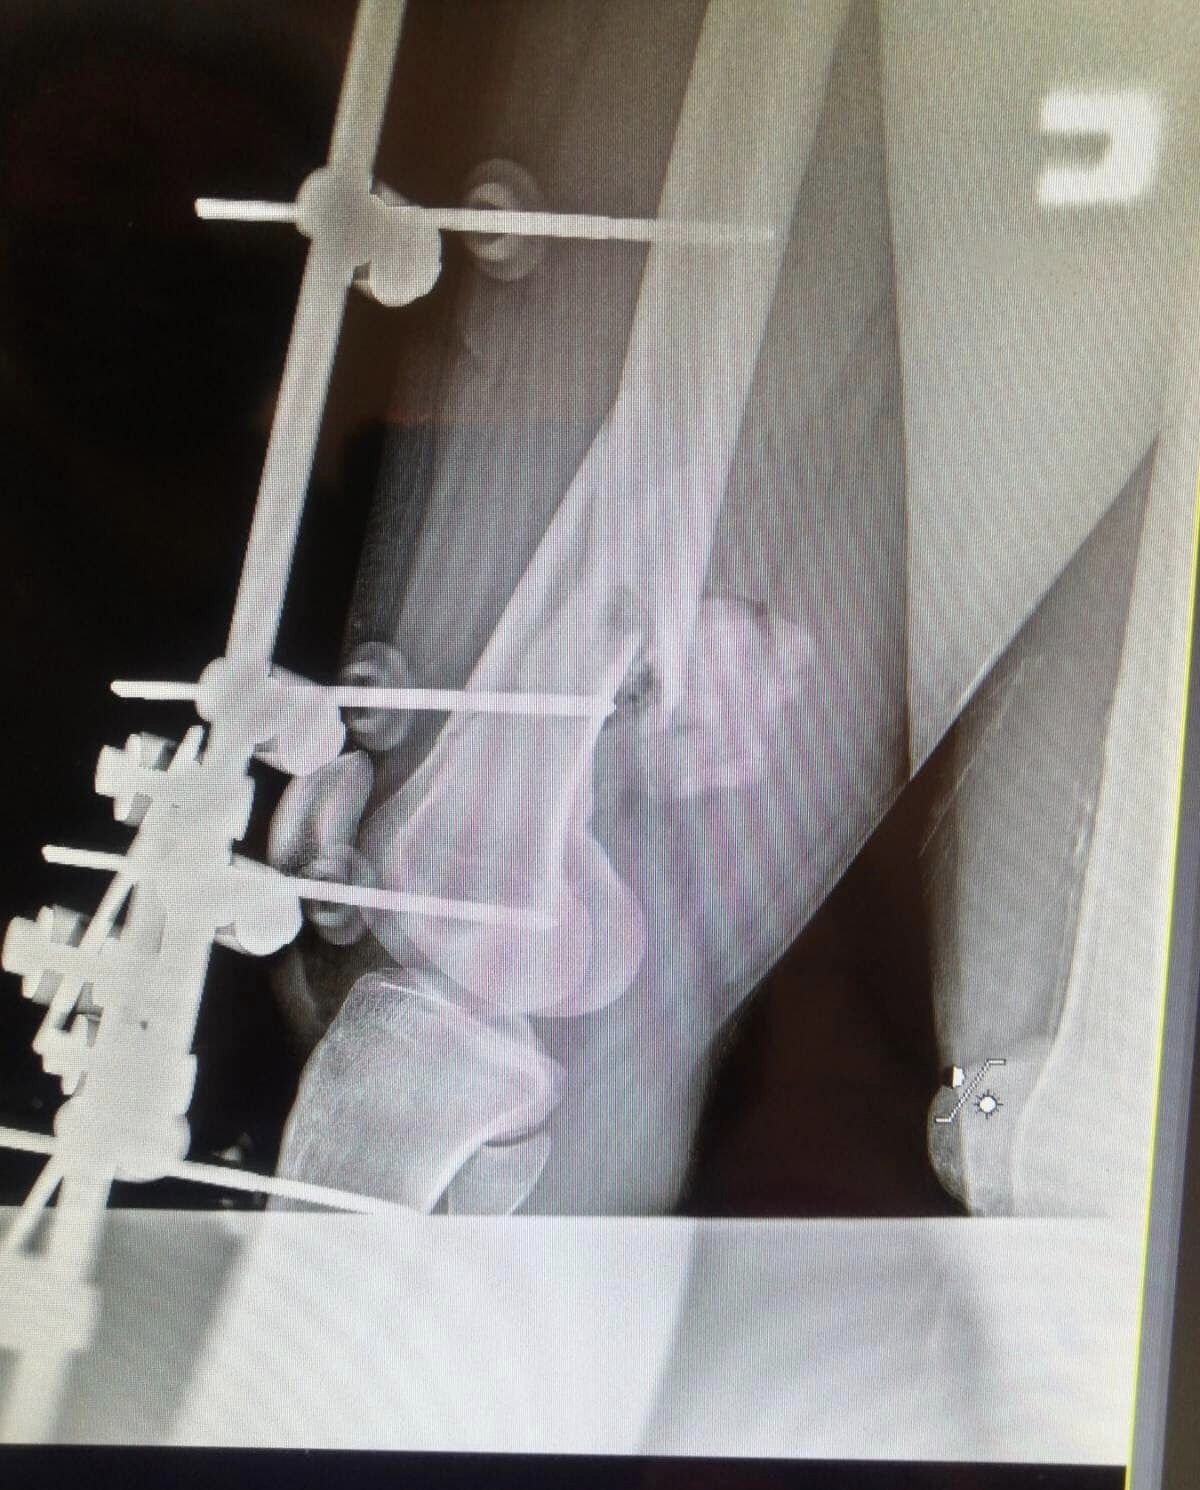

Досвідчені хірурги провели складну операцію, дістали уламки та встановили апарат для фіксації перелому. Біль одразу залишив хлопця. Зараз він відновлює сили та загоює рани. Лікарі турбуються про його здоров‘я, а піклуванням оточує сім‘я. Родина Михайла постійно знаходиться поряд.